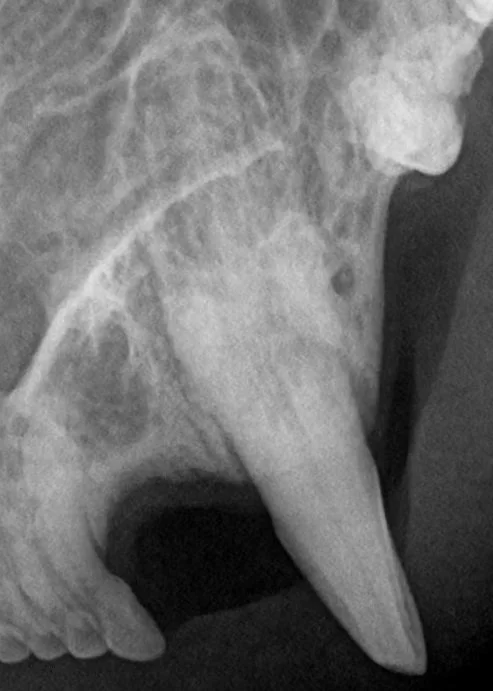

Xray of the upper left canine with a moth eaten root.

On xray we can see the root of the canine has become moth eaten and resorbed - this tooth is very unhealthy and requires extraction.